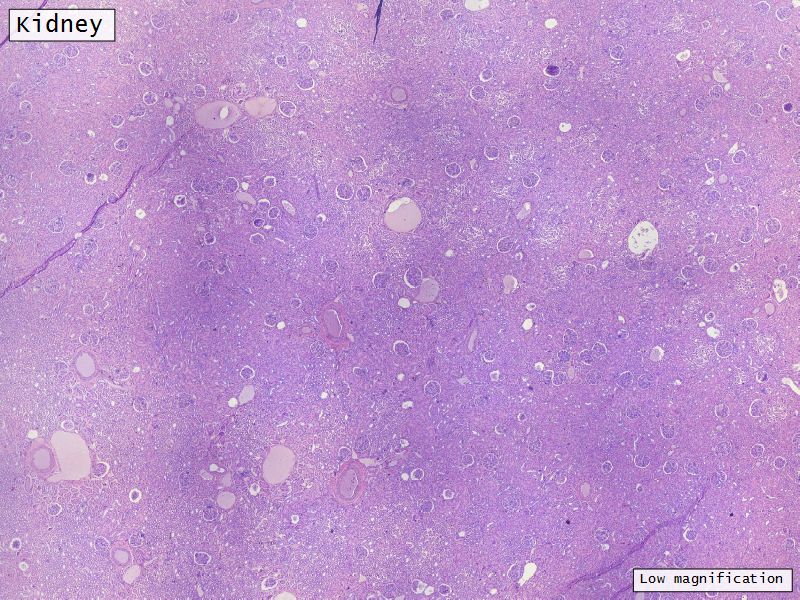

Appearance

- Cortex

- Renal corpuscles

- Convoluted tubules

- Medulla

- Loops of Henle

- Collecting tubules

Proximal convoluted segment

- Longest part of nephron

- Wide triangular cell

- Spherical nucleus

- Indistinct cell borders

- Luminal surface

- Striated brush border

Loop of Henle - thin

- Narrow lumen

- Thin wall

- Squamous epithelium

- Looks like capillaries

Loop of Henle - thick

Continuation of descending and ascending tubuliDistal convoluted tubuli

- Joins collecting tubule

- Cuboidal epithelium

- Light stained

- Wide looking lumen

- Indistinct borders

Collecting tubule

- Cuboidal to columnar epithelium

- Distinct lateral borders

Main collecting ducts

- Wide lumen

- Pale staining columnar cells